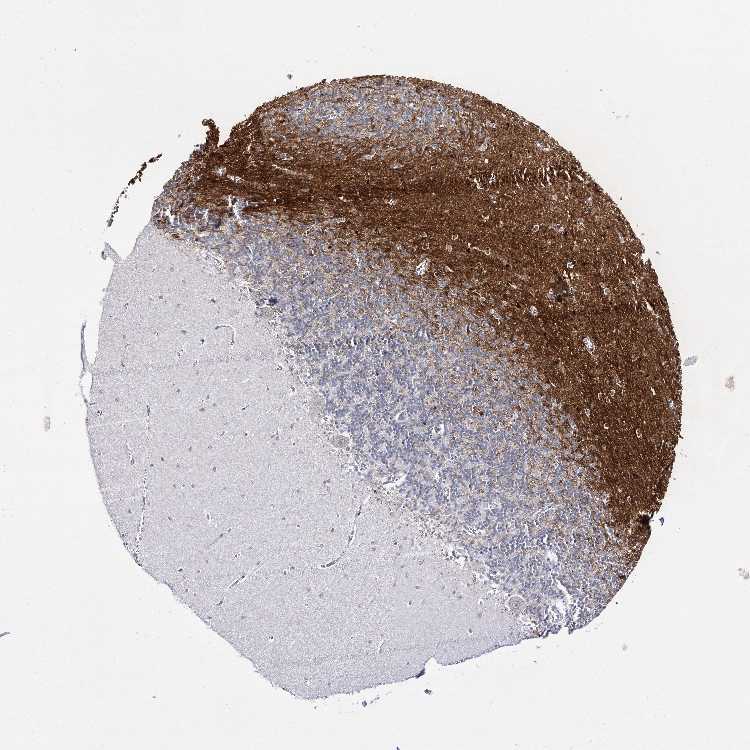

CEREBELLUM - Antibody stainingi

Antibody staining in the annotated cell types in the current human tissue is reported as not detected, low, medium, or high, based on conventional immunohistochemistry profiling in selected tissues. This score is based on the combination of the staining intensity and fraction of stained cells.

Each image is clickable and will lead to virtual microscopy that enables deeper exploration of all samples and also displays staining intensity scores, fraction scores and subcellular localization as well as patient and tissue information for each sample.

Antibody HPA034574

Purkinje cells Not detected

Cells in granular layer Not detected

Cells in molecular layer Not detected